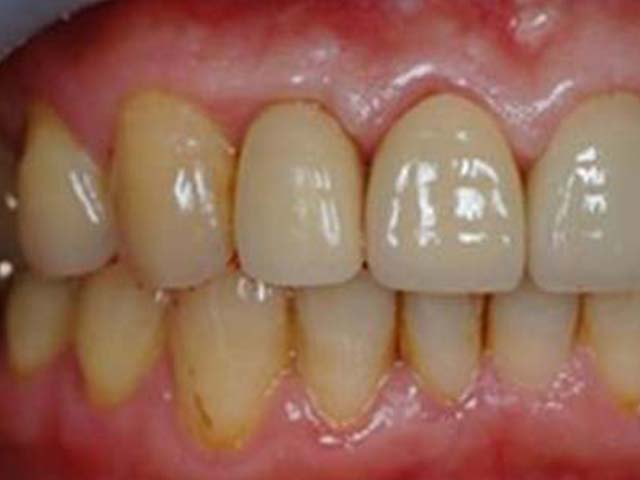

人工植牙 首頁 案例分享 人工植牙 前牙植牙 更多 牙橋嚴重蛀牙,即拔即種,避免二次傷口 更多 齒槽骨保存術+植牙 更多 前牙審美植牙 更多 微創植牙 更多 小臼齒植牙 更多 即拔即種 更多 鼻竇增高術(垂直)+植牙 更多 鼻竇增高術(側窗) 更多 «1»